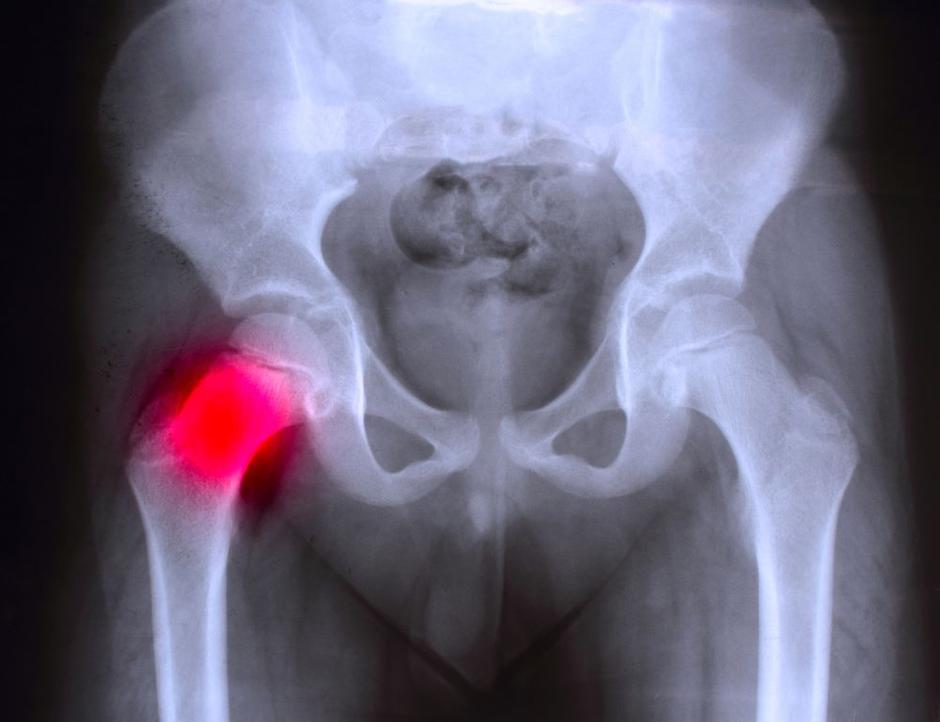

Displazija kolka je stanje pri katerem glavica stegnenice ni pravilno poravnana z acetabulumom (kolčno ponvico), kar povzroča nestabilnost sklepa. Stanje se pri pacientih kaže z bolečino, omejeno gibljivostjo in drugimi degenerativnimi spremembami.

Kolk je eden najmočnejših sklepov v človeškem telesu. Tvorijo ga glavica stegnenice in globoka jamica medenice imenovane acetabulum. Stabilnost sklepa zagotavljajo močni ligamenti in gosta vezivna kapsula, ki obdajajo celoten sklep.

Na robu acetabuluma se nahaja labrum, hrustančni obroček, ki povečuje globino sklepne jamice in pripomore k stabilizaciji glavice stegnenice.

Ena izmed njih je ti. displazija, ki povzroča, da se sklepna glavica in ponvica ne prilegata pravilno. To vodi do obrabe hrustanca, bolečin in zmanjšane gibljivosti.

Pri displaziji kolka se pojavijo očitne anatomske spremembe, ki prizadenejo kolčni sklep in okoliške strukture. Najprej pride do nepravilnega razvoja acetabuluma, ki zaradi slabe poravnave s stegnenično glavico ostane plitek sploščen.